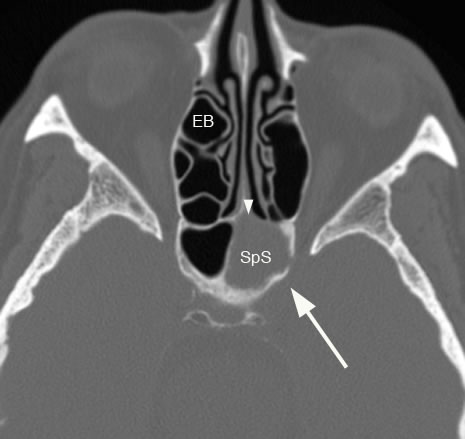

Axial image with large arrow showing left sphenoid sinus (SpS) disease with ostruction of the ostium (arrowhead). (EB: ethmoid bulla)